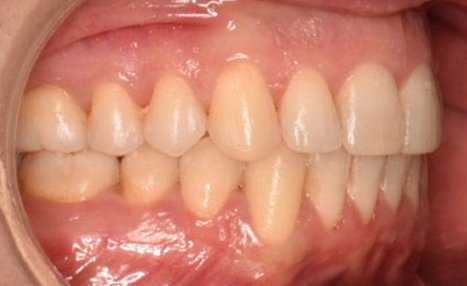

After 16 months of treatment, the transformation was evident:

(Image: 2 years after finishing)

This case demonstrates how precision in bracket placement and variable torque selection with Damon Ultima can fundamentally influence treatment efficiency and outcomes. By addressing torque control and smile arc from the very first appointment, round-tripping was minimized, biomechanics were optimized, and finishing required only fine adjustments rather than compensations.

The Damon Ultima system allowed the clinician to align facial esthetics, occlusal function, and long-term stability in a challenging adult case, underscoring the value of intentional planning and execution.